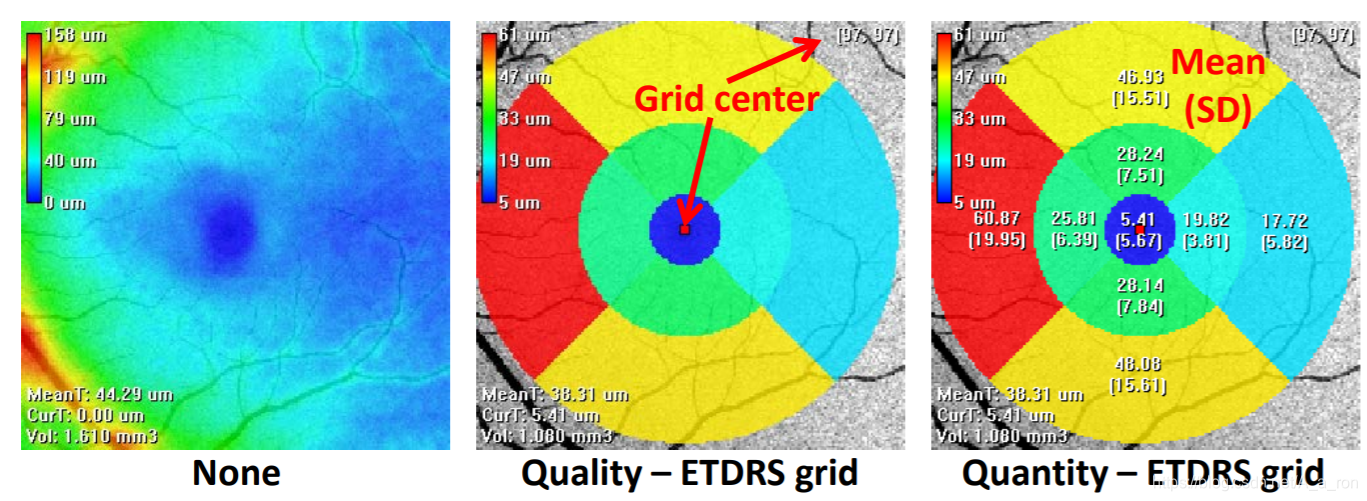

视网膜厚度分析:

ETDRS分区分析:

ReLayer: 一个免费且在线的用于眼科OCT影像分析的跨平台工具。目前的分析主要包括视网膜层次分割和厚度分析。如层次分割:

厚度分析: